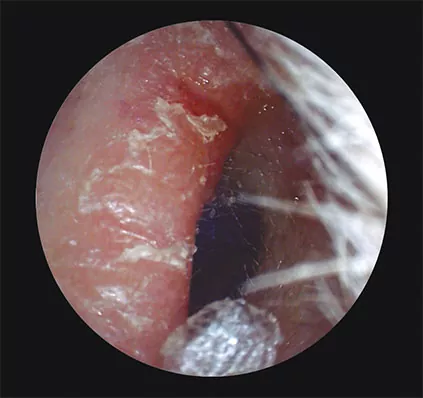

Estenosis: estrechamiento del CAE. Puede ser debido a una atresia completa o un colesteatoma, que producirá una pérdida conductiva de hasta 60 dB (Fig. 1.C).

Fig. 1. C. Estenosis del conducto auditivo del oído derecho. El estrechamiento de las paredes del conducto es tal que impide la correcta visibilidad del tímpano.